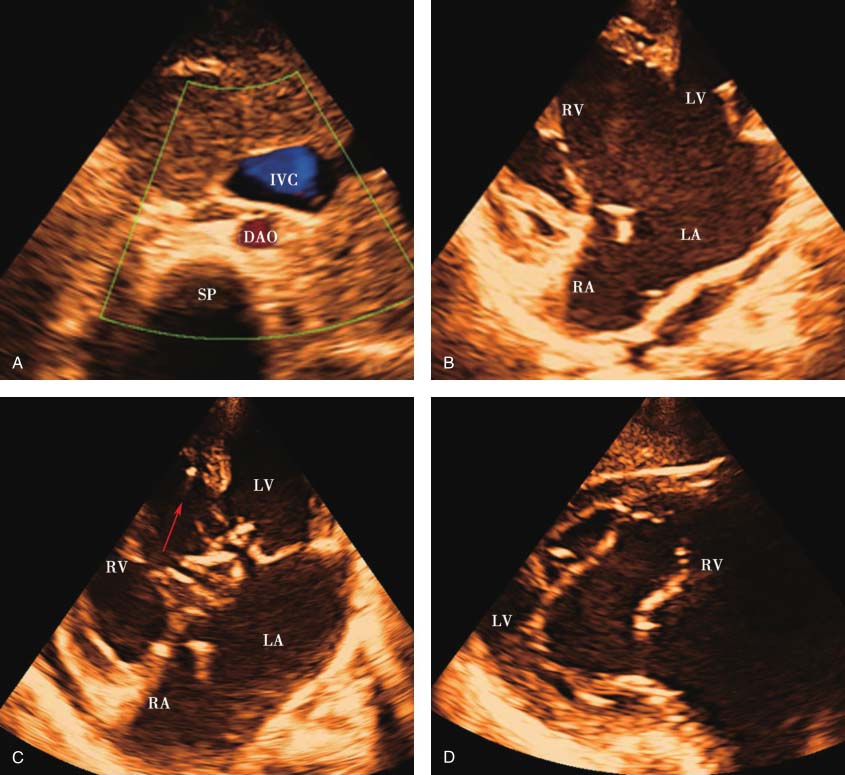

右心、左心房扩大。室间隔与左心室室壁厚度正常,运动幅度正常。房间隔下部至室间隔上部可探及宽约40mm回声失落,探及共同房室瓣环及共同房室瓣启闭,前桥瓣腱索骑跨,系于室间隔右心室面。流出道切面见肺动脉和主动脉均发自解剖学右心室,肺动脉在左,主动脉在右,肺动脉瓣增厚,回声增强,开放受限。左心房房壁未探及肺静脉切迹,其后方探及四支肺静脉均引流入共同肺静脉腔。主动脉弓降部未见明显异常。心包无异常。见图13-1。

图13-1 患儿超声心动图表现

A.上腹部横切面显示腹主动脉和下腔静脉均位于脊柱左侧,下腔静脉在前,腹主动脉在后;B.四腔心切面显示十字交叉结构消失,房间隔下部至室间隔上部可探及回声失落,并见共同房室瓣启闭;C.四腔心切面显示前桥瓣腱索骑跨,并系于室间隔右心室面(箭头);D.剑突下切面瓣口水平心室短轴切面显示共同房室瓣启闭;E.流出道切面显示肺动脉和主动脉均发自解剖学右心室;F.肺动脉瓣增厚,回声增强,开放受限,呈圆顶征(箭头);G.舒张期肺动脉瓣反流速度约360.82cm/s,估测平均肺动脉压约52.08mmHg;H.左心房房壁未探及肺静脉切迹,左心房后方探及四支肺静脉引流入共同肺静脉腔。

上腹部横切面显示水平肝,无脾,腹主动脉和下腔静脉位于脊柱同侧,由此可判断患者为右心房异构。二维超声显示四腔心切面十字交叉结构消失,房间隔下部至室间隔上部可探及回声失落,无正常的相互独立的左右心室流入道,探及共同房室瓣环和共同房室瓣启闭,前后桥瓣之间未粘连,前桥瓣腱索系于室间隔右心室侧,可诊断为完全型心内膜垫缺损,Rastelli分型为B型。主动脉和肺动脉起始部交叉包绕现象消失,二者均发自右心室,起始部平行走行,诊断为DORV,且肺动脉瓣存在狭窄。对右心房异构患者应特别关注是否存在肺静脉异位引流,重点观察左心房房壁是否有肺静脉切迹,是否存在肺静脉腔。